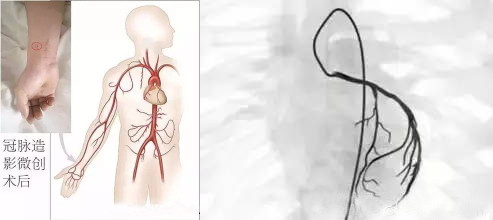

冠状动脉造影多取四肢动脉为入路,尤其经皮穿刺桡动脉最常用,也可穿刺股动脉或肱动脉

选择性冠状动脉造影是利用血管造影剂,通过特制的心导管经皮穿刺上肢桡动脉或者下肢股动脉,沿降主动脉逆行至升主动脉根部,然后探寻左或右冠状动脉口插入,注入造影剂,使冠状动脉显影,清楚地将整个左或右冠状动脉的主干及其分支的血管腔显示出来。